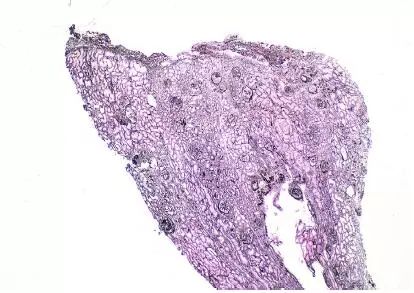

CNI肾毒性导致的血管收缩无形态学变化。急性CNI肾毒性特征包括:近端肾小管上皮细胞空泡化,大小一致;血管损伤,平滑肌细胞丢失;肌细胞胞浆空泡化;细胞坏死或凋亡退化。肌细胞损伤最终发展为局灶性结节性玻璃样变和透明样变,可延伸至小动脉和动脉血管壁整个中层。CNI肾毒性还可引起血栓性微血管病变(TMA),主要累及小动脉和肾小球毛细血管袢。慢性CNI毒性特征为:条状间质纤维化,肾小管萎缩。

图3 CNI肾毒性透明样变延伸至动脉中层和节段性肾小球硬化(Jones 银染)

图4 CNI肾毒性结节性透明样变延伸至肾小叶间动脉中层(Jones 银染)

图5 CNI肾毒性结节性透明样变延伸至动脉中层(PAS染色)